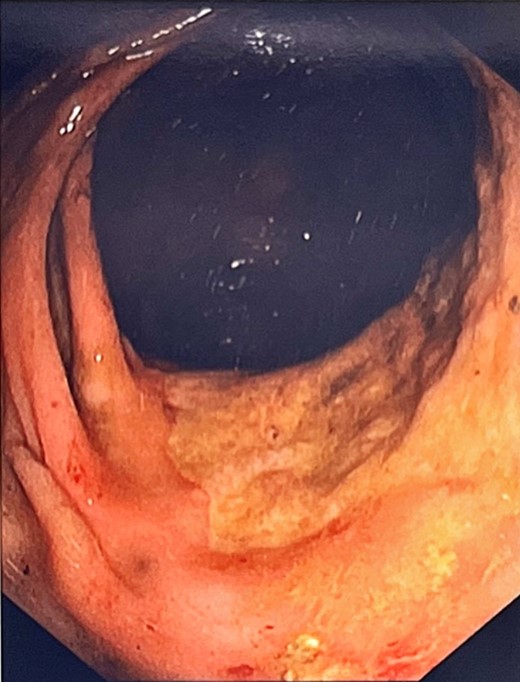

An indwelling catheter drained 900 ml, alleviating discomfort. She was commenced on daily aperients and enemas allowing passage of a large amount of stool, however a progress abdominal x-ray showed ongoing large bowel dilatation. She underwent a colonoscopy for both diagnostic and therapeutic purposes, with manual disimpaction of a 20 × 15 cm faecolith in the sigmoid proximal to a stenosed fibrotic segment at 21 cm. Other findings included patulous non-contractile large bowel with redundant loops (Fig. 2). Biopsies were obtained from the stenosed area at 21 cm and the ano-rectal junction. Histopathology was significant for absence of ganglion cells on both haematoxylin and eosin stain as well as calretinin immunostaining, confirming the suspicion of AHD.